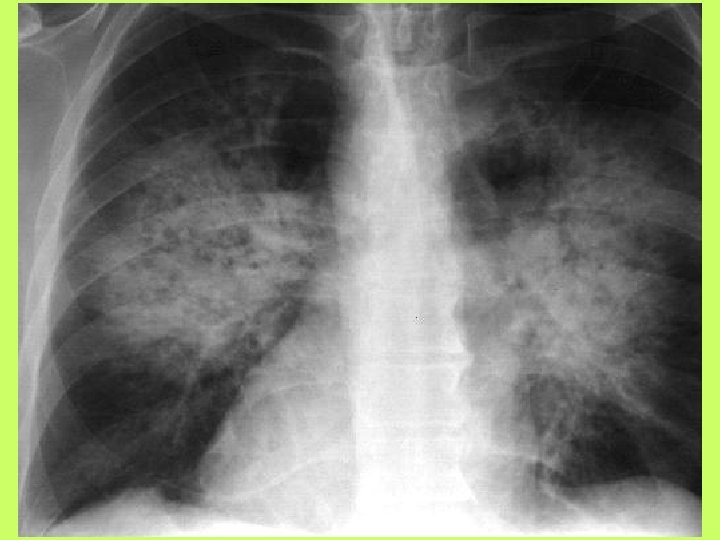

Noninvasive cardiac diagnostic studies 1 - EKG 2 -Chest X ray 3 -Exercise tolerance

Noninvasive cardiac diagnostic studies 1 - EKG 2 -Chest X ray 3 -Exercise tolerance test(ETT) 4 -Echocardiography transthoracic-trans esophagial 5 -Stress echocardiography 5 -Radionuclid imaging 6 -Cardiac catheterization